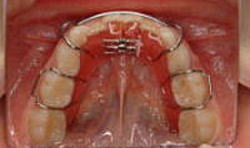

デーモンブラケットの利点と欠点

![]() |

永久歯が生えそろった時期 |

利点 |

ブラケット(歯についているボタンのようなもの)をワイヤーに固定しないため、歯の痛みが少なく、比較的短期間で治療が終了します。 |

欠点 |

床矯正とは違い、自分では取り外しが出来ません。 |